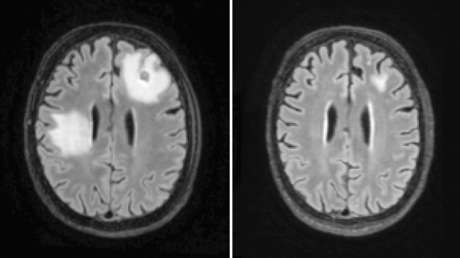

Un absceso cerebral es una acumulación de pus y material infectado en el tejido del cerebro. Pueden causar convulsiones, trastornos visuales o cambios en la visión, el habla, la coordinación o el equilibrio. Su tratamiento a menudo incluye procedimientos quirúrgicos.